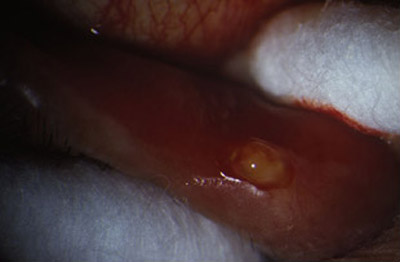

La presencia de un canalículo superior o inferior eritematoso, turgente, a veces doloroso, lleno de abundante material purulento caseoso, de color verde claro, caracteristicamente producido por estos microorganismos, nos lleva al diagnóstico.

El punto lagrimal inferior puede estar vertical, en un ligero ectrópion medial. Al realizar presión sobre el canalículo afectado entre dos hisopos de algodón, y repitiendo esta maniobra varias veces en la lampara de hendidura, se puede obtener abundante material caseoso sin dificultad.

Bajo microscopio (a 16 aumentos) y con anestésia local, Xilocaina al 2% con adrenalina, inyectada sub dérmica en el tercio interno del parpado inferior, canto medio, procedemos a evertir un poco el borde palpebral inferior con un aplicador de algodón, para exponer el area marsupializada del canalículo, dejando la luz mucosa ampliamente expuesta.